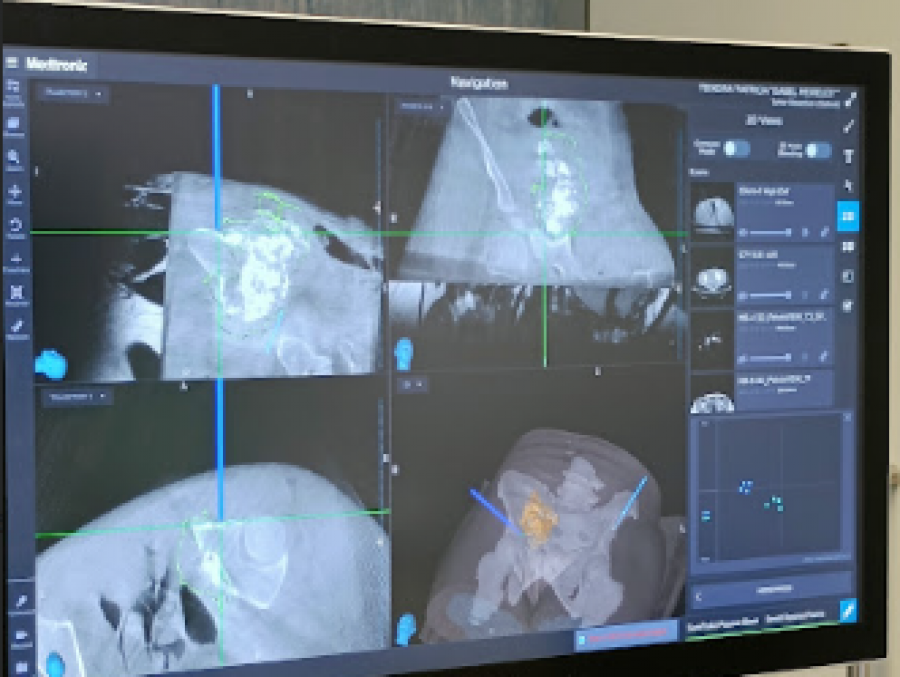

O Centro Hospitalar Universitário de Santo António realizou, recentemente, uma intervenção inédita em Portugal, a primeira cirurgia de resseção tumoral assistida por navegação computorizada.

O Santo António é Centro de Referência de Sarcomas de Partes Moldes e Óssea.